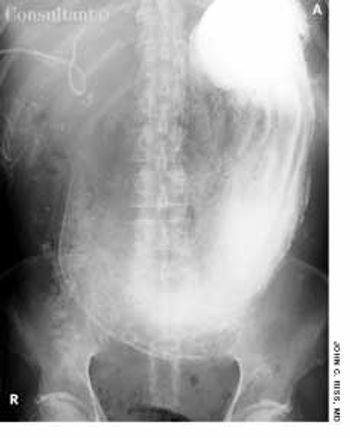

A 31-year-old man with a history of traumatic brain injury was hospitalized because of failure to thrive, constipation, and intermittent diarrhea with soiling.